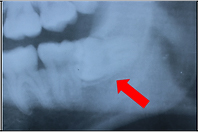

親知らずが生えていることが分かっている方は、一度歯科医院に行ってそのままにしておいてよいか診てもらいましょう。

下の写真は、親知らずが横向きに生えていて隙間があります。

下の写真は、その隙間に食べかすが入ってしまっています。

この隙間は下の方が深歯ブラシが届かず、このままでは親知らずと手前の歯が2本とも虫歯になってしまうので抜いたほうが良いケースです。